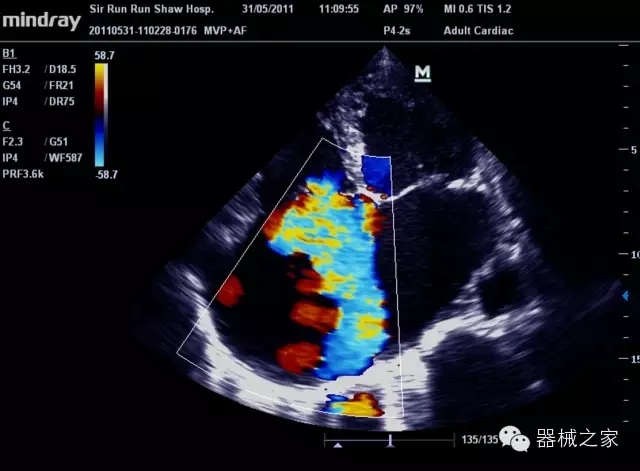

經典產品:M7(星鉆)

臨床圖片賞析

產品特點

·裝載有采用Multi-Core多核處理的非嵌入式平臺,成像效率大大提高,并且能夠給用戶帶來高速、多任務并行信號處理體驗;

·優(yōu)秀的圖像效果、強大的功能體驗、豐富的探頭選擇、合理的便攜式設計,全中文顯示及病人管理界面,使得M7在任何場合、任何時候都能快速響應更好的心血管、腹部、婦產、小器官等常規(guī)超聲檢查以及肌骨、神經、顱腦、術中等新興領域的使用需求;

8倍波束并行處理系統(tǒng)

·在便攜式緊湊平臺上采用更多倍波束并行接收信號處理模式,無論二維還是彩色血流圖像狀態(tài)下,擁有更靈敏的回波頻移捕獲能力,大大提高時間分辨率,尤其使得心血管表現更為突出;

PSHI?寬帶頻移諧波技術

·在普通組織諧波的基礎上,通過精確控制的波束形成器,發(fā)射兩組具有相位偏差反向的信號,并采用并行信號處理,數字化合成并采樣回波信號,在高靈敏度的濾波器的處理過程中獲取更純凈的諧波信號,使圖像具有更加出眾的細節(jié)分辨率;

iClear®+iBeam?

·智能化按線復合多角度獲取聲束的原始信號,配合智能化的斑點噪聲識別及控制處理技術,整體提高組織結構細節(jié)分辨率,任何時候都能快速響應,更好的滿足心血管的使用需求;

支持全新3T工藝探頭群

·包括探頭材料、結構設計、加工工藝三方面的革新技術給圖像帶來品質的飛躍;

CFDA注冊證編號

·粵食藥監(jiān)械(準)字20132230475